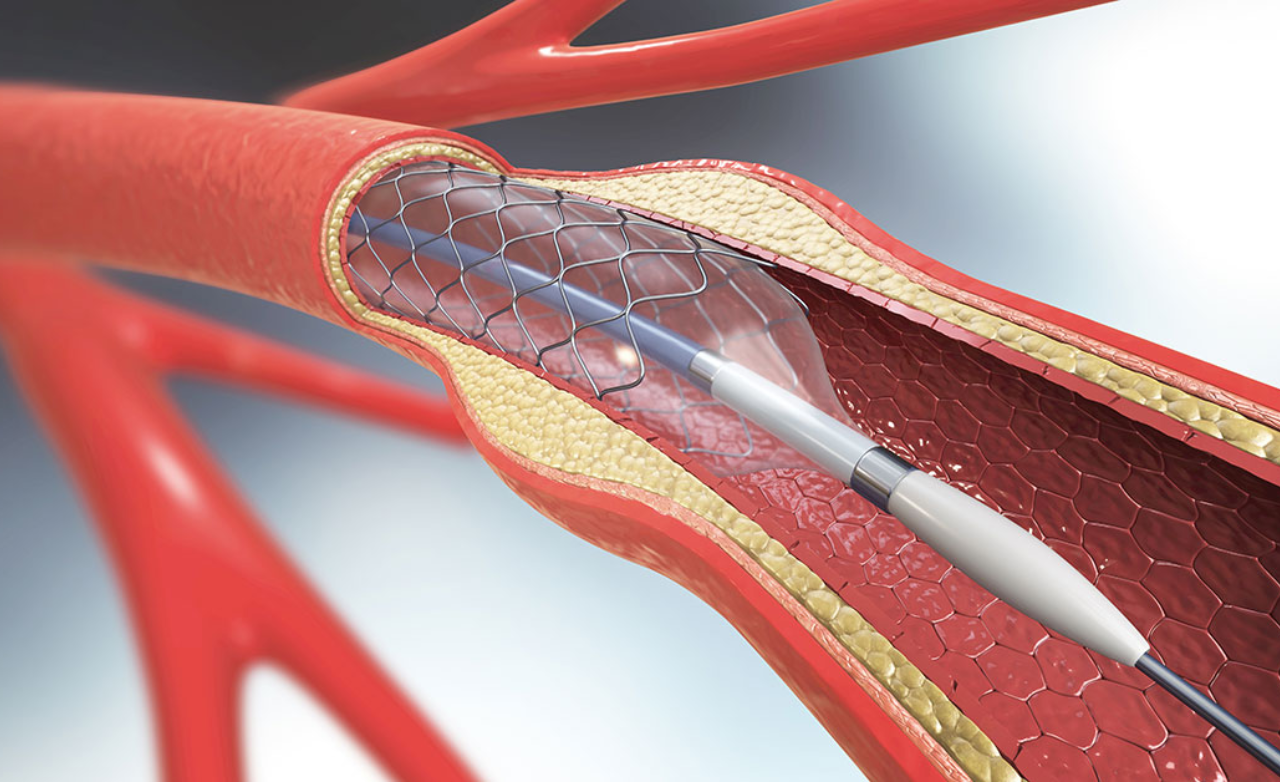

Opens narrowed arteries supplying the brain, improving blood flow and reducing stroke risk through a precise, minimally invasive procedure.